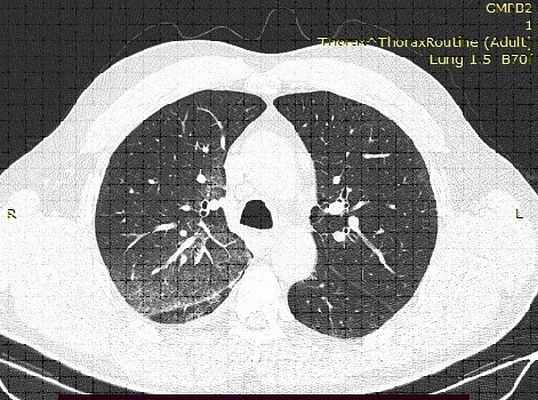

КТ-картина имбибиции верхней доли правого легкого

Золотым стандартом в диагностике легочного кровотечения является выполнение компьютерной томографии с внутренним контрастированием (Ангио-КТ), позволяющее как оценить состояние легочной паренхимы, так и определить локализацию субстрата для кровотечения, а также выявить патологические бронхиальные артерии, диагностировать аномалии и пороки развития легких и их сосудов. Одной из важнейших задач при выполнении Ангио-КТ является оценка проходимости ветвей легочной артерии, поскольку нередко легочное кровотечение является следствием развития ТЭЛА, и подходы к лечению таких пациентов принципиально отличаются. В тоже время, противопоказаний к выполнению экстренной Анго-КТ немного, и для их выявления, порой, достаточно подробного сбора анамнеза и выполнения биохимического анализа крови.